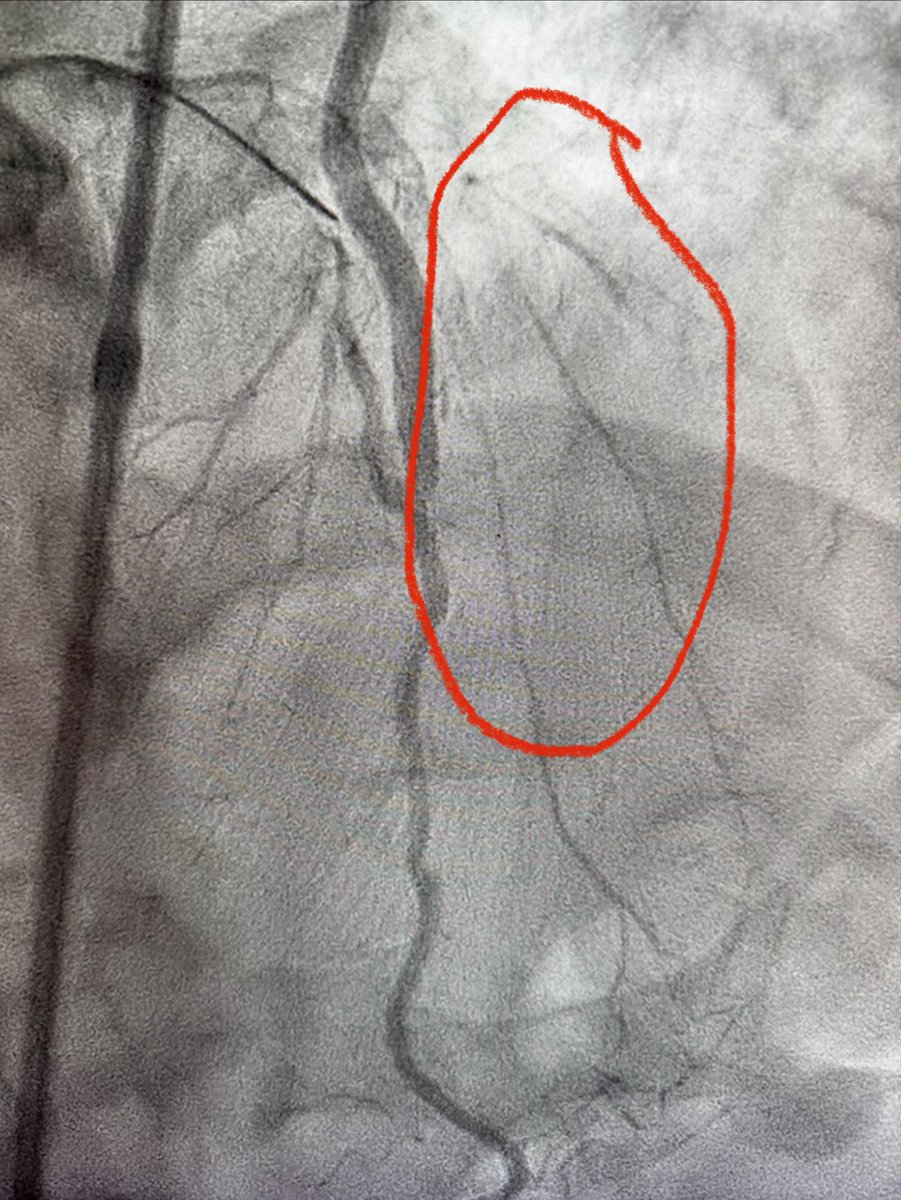

CTO LAD 🔹Dual injection 🔹RCA with wire protection 🔹LAD with microcatheter 🔹Trapping technique to secure the wire 🛑 Always secure the donor first 📍 Microcatheter = Stability + Roadmap ⚠️ Don’t rush the setup, good prep = smoother case 😁 Happier than the patient. #CTO…